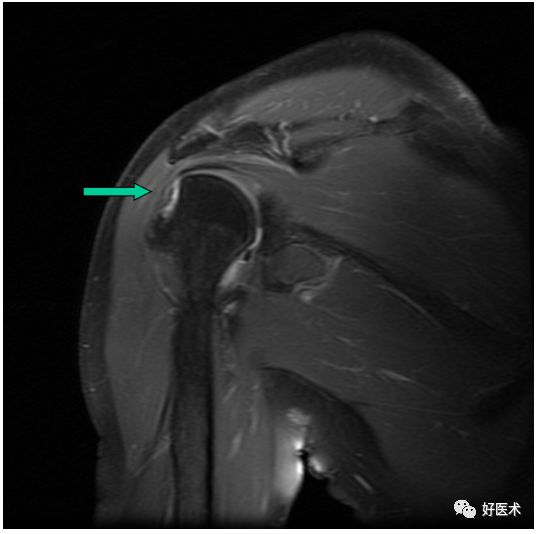

MR间接关节造影1.5T冠状面T1W脂肪抑制

Hill-sachs,Bankart,关节囊损伤

SLAP、Bankart合并Hill-Sach损伤